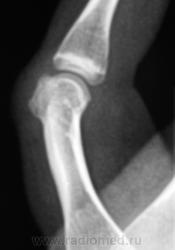

Судя по-всему тип роста экспансивный ,симпотом новообразования. Кортикальный слой как бы переходит на новообразование, контур его четкий, структура губчатая без включений, кость не вздута, окружающая ткань на мой взгляд не изменена ,окружаюшщие мягкие ткани равномерной интенсивности. Губчатая остеома?

+ за остеому

Следовательно, можно писать губчатую остеому?